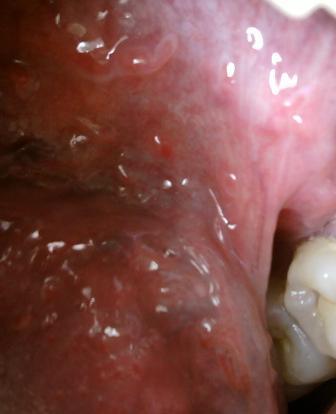

哪些症状可以证实已经患上了尖锐湿疣尖锐湿疣现在的发病率是很高的,因此建议大家在平时应该注意做好必要的防护工作,尖锐上湿疣在发病之前具有一定的潜伏期,但是在潜伏期是没有任何的症状的,所以也就不容易被人们察觉。

哪些症状可以证实已经患上了尖锐湿疣由于尖锐湿疣是比较顽固的,所以建议大家在治疗期间应该注意养成一些好的习惯,尖锐湿疣的发病率是比较高的,可殃及任何年龄段男女性,主要以性行为频繁男女性为主。所以平时生活中大家一定要洁身自爱。临床上主要有以下几种传染途径:直接接触传染,间接接触传染和母婴传染等等。年轻的男女是尖锐湿疣发病的高发人群。男子好发部位依次为冠状沟、龟头、包皮、包皮系带、尿道口,女性依次为大小阴、处女膜残端、尿道口、下联合、子宫颈、阴道壁、肛周、阴阜等